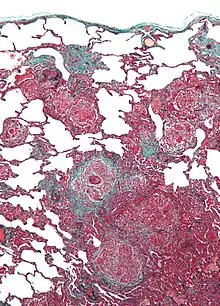

| Micrograph of hypersensitivity pneumonitis, the histologic correlate of bird fancier's lung. Lung biopsy. Trichrome stain. | |

Lung biopsy usually reveals non-necrotizing granulomatous inflammation.[7] It also shows "foamy" macrophages and crystals of oxalic acid.[3] Hyperplasia tends to occur in type 1 pneumocytes and not in type 2 pneumocytes.[3]